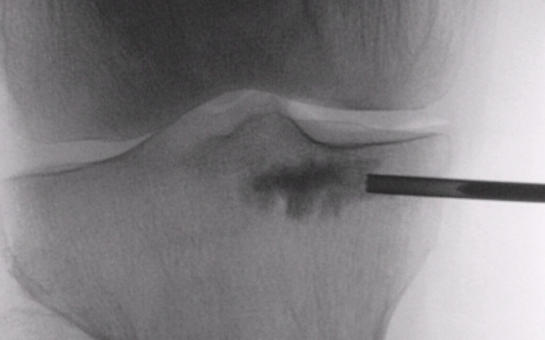

Çocuk ve Ergenlerde Ön Çapraz Bağ Yaralanmalarının Tedavisi

Genç yaşlarda spora katılımın artması ve giderek daha rekabetçi hale gelmesi, büyümesi tamamlanmamış çocuk ve ergenlerde ön çapraz bağ yaralamalarının görülme sıklığını artırmıştır. Çocuklarda ön çapraz bağ yaralanmaları kemik yapışma yerinden kopma kırıkları şeklinde olabileceği gibi, bağın gövdesinden olan yırtılmalar şeklinde de karşımıza çıkabilir.